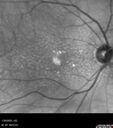

83 year old man Retired aerospace engineer. Blurred vision in both eyes with complex eye history. No acute changes noted by patient. Prior macula-on retinal detachment repair in the right eye a year ago (buckle, vitrectomy, laser, gas, ST Kenalog). Medical Hx: Hypertension, Systemic. Hyperlipidemia. Asthma. Surgical Hx: left shoulder ac separation 2013. Turp 2010. Systemic Meds: Lisinopril, 10 mg oral tablet bid. simvastatin QD. muscinex DM QD. Metformin 100 MG QD. Allergy Medicine. HCTZ QD. PRILOSEC QD. MYBETRIC. MONTULAKAST. Aspirin 81 mg. QUETISPINE 150 MG QD. ESATATOPRAM 20 MG QD. VA OD: Dcc20/50 VA OS: Dcc20/50-2 IOP: TP: OD:15 OS:16 Converted to wet AMD after a single Izervay Treatment

Conversion to Wet AMD after Izervay27 views83 year old man whose left eye had minimal GA and converted from dry to wet AMD after a single Izervay treatment00000